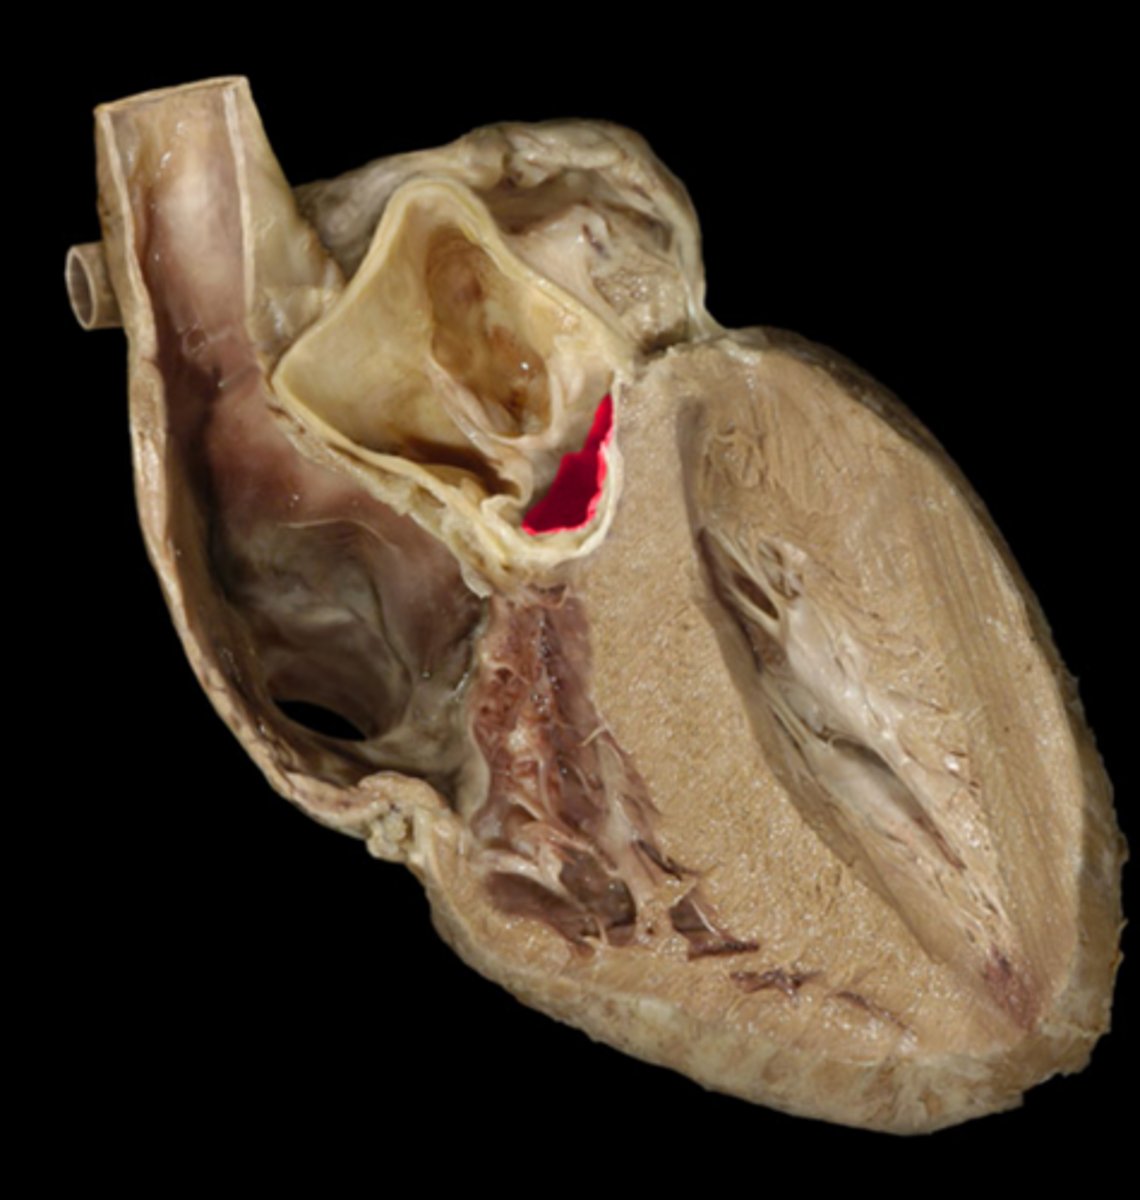

Interatrial septum

collective Structure; pinch between left and right atrium

Fossa ovalis

depression

in R atrium, pinto bean buried in R atrium

Pectinate muscle

st

stretch jeans on inside of right atrium

webbing on wall of R atrium

Sinus venarum

surface; on inside of right atrium, smooth part, by fossa ovalis

Right atrioventricular orifice

Space, stick probe from atrium to ventricle to open doorway

tricuspid valve

Structure; closed door, three flaps